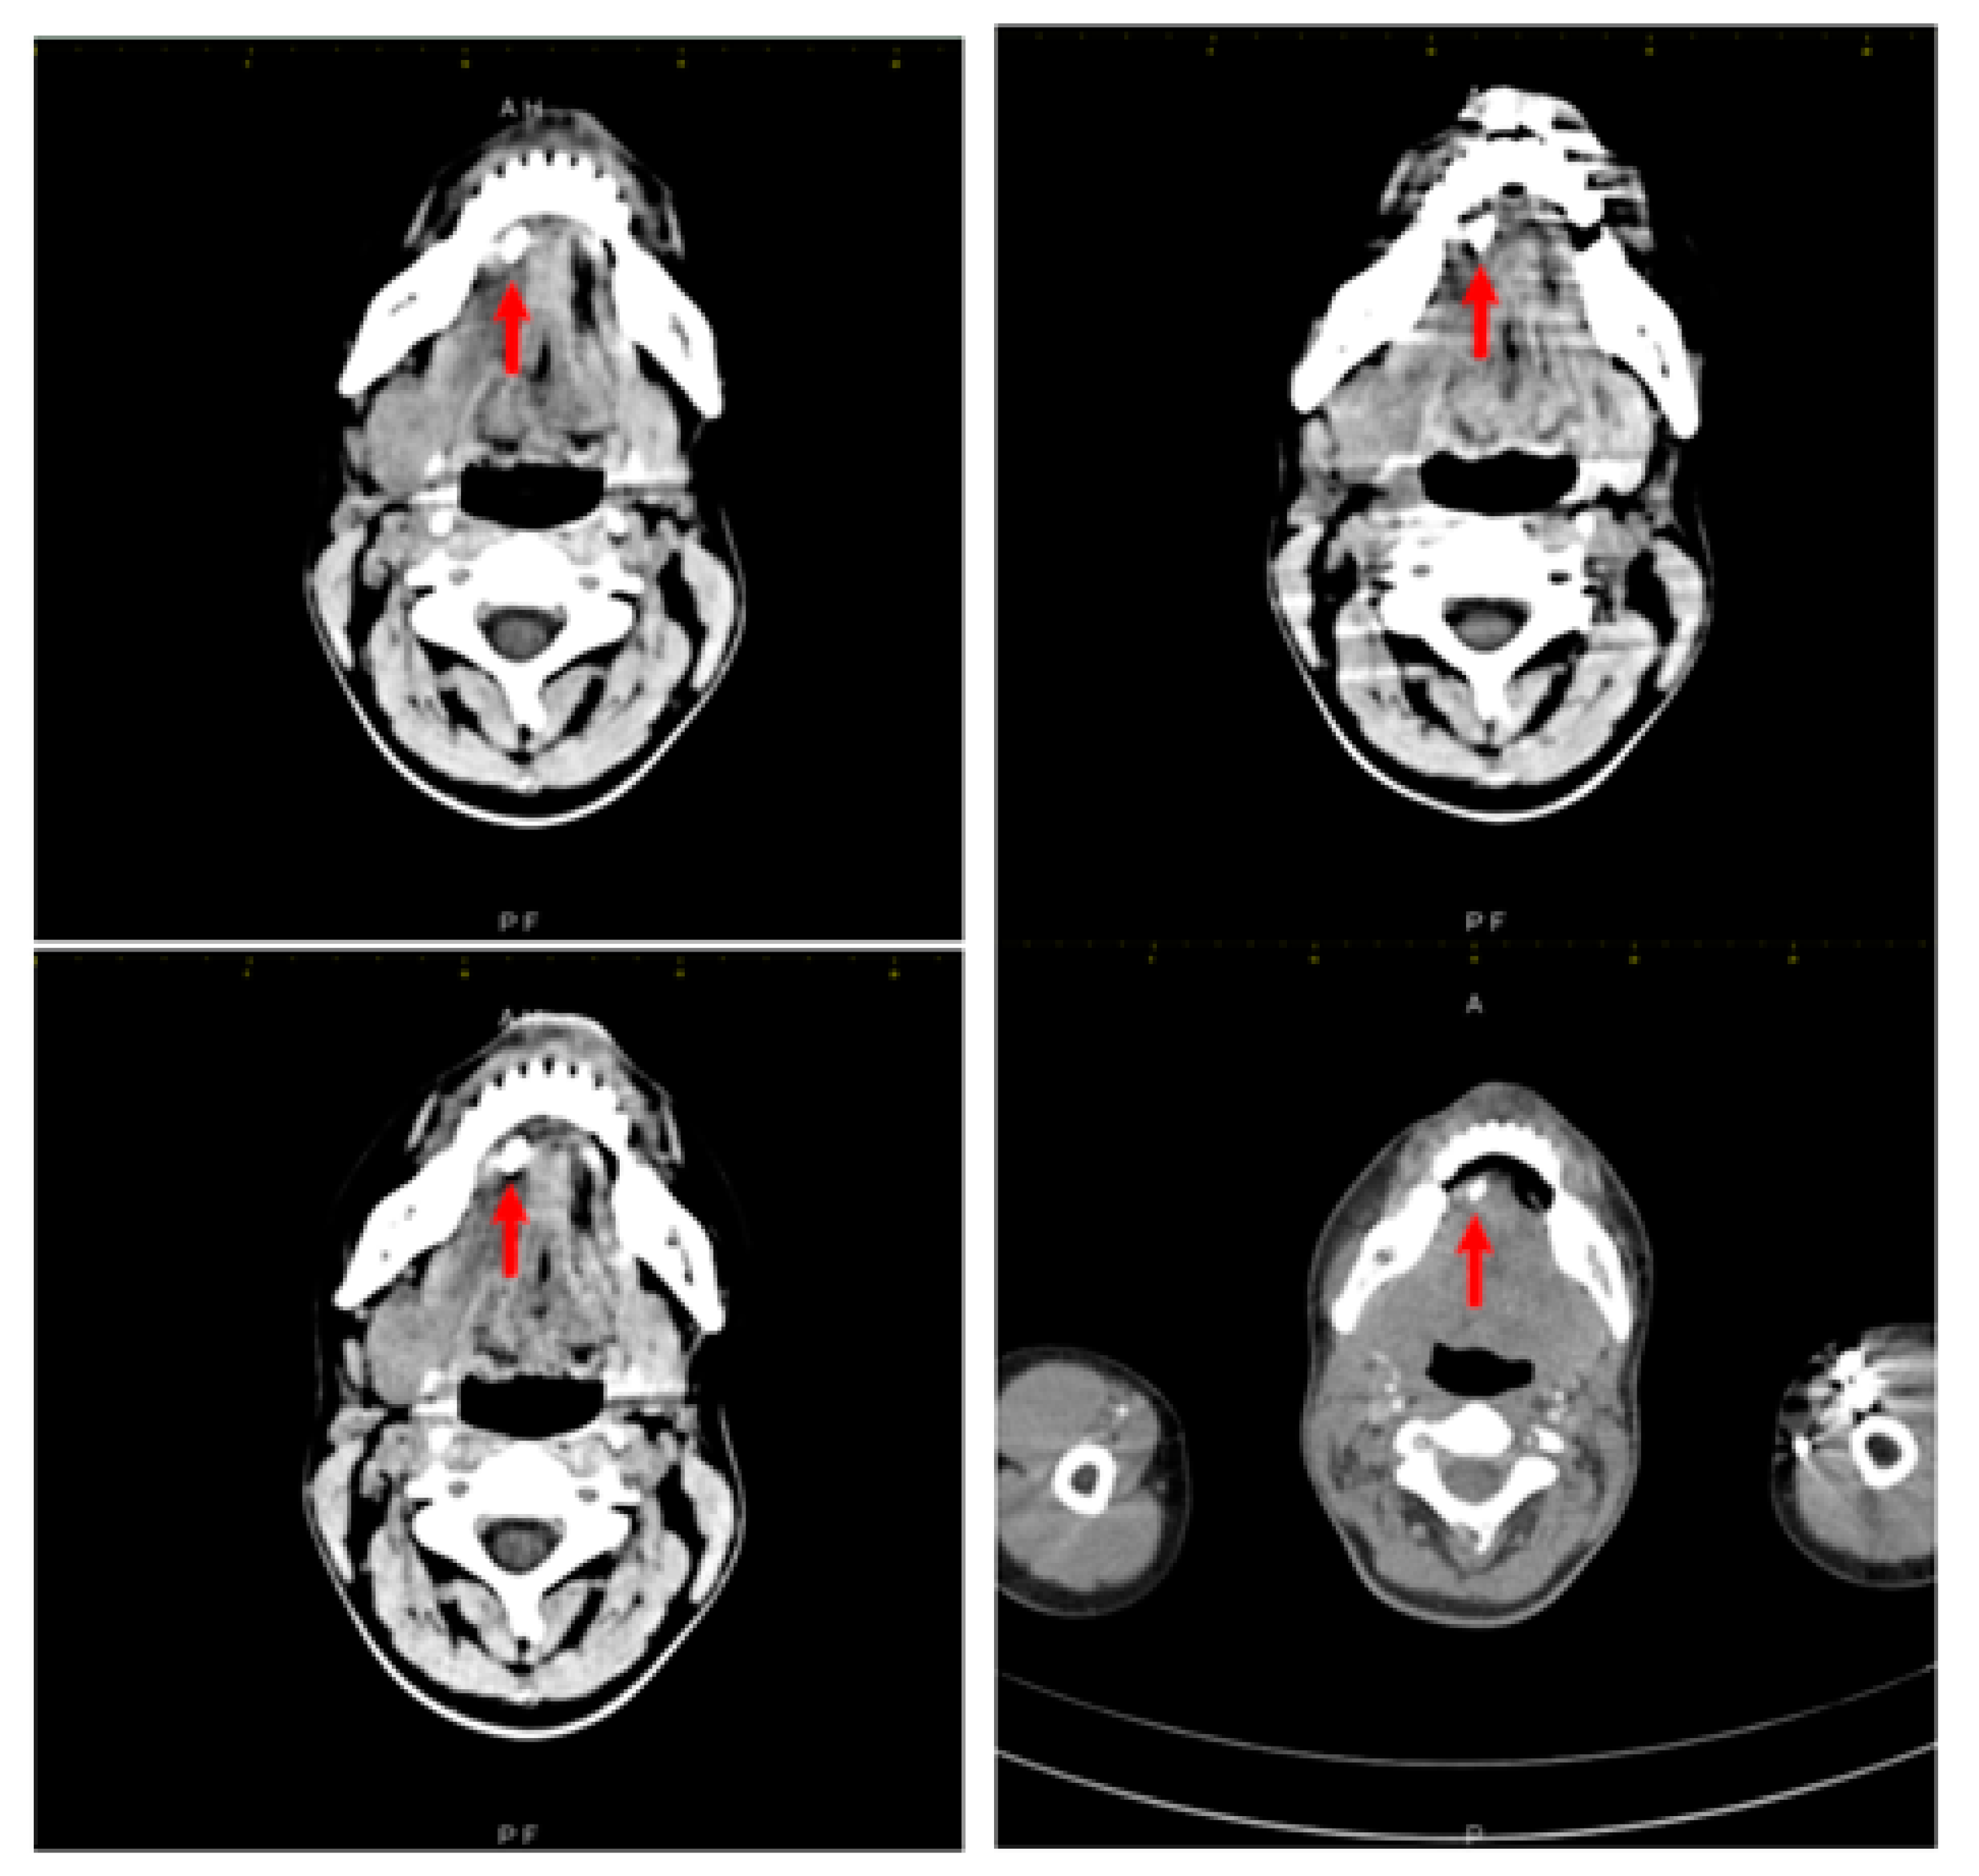

Multiple Faces of Cervical Lesions in Children

2. Case Report